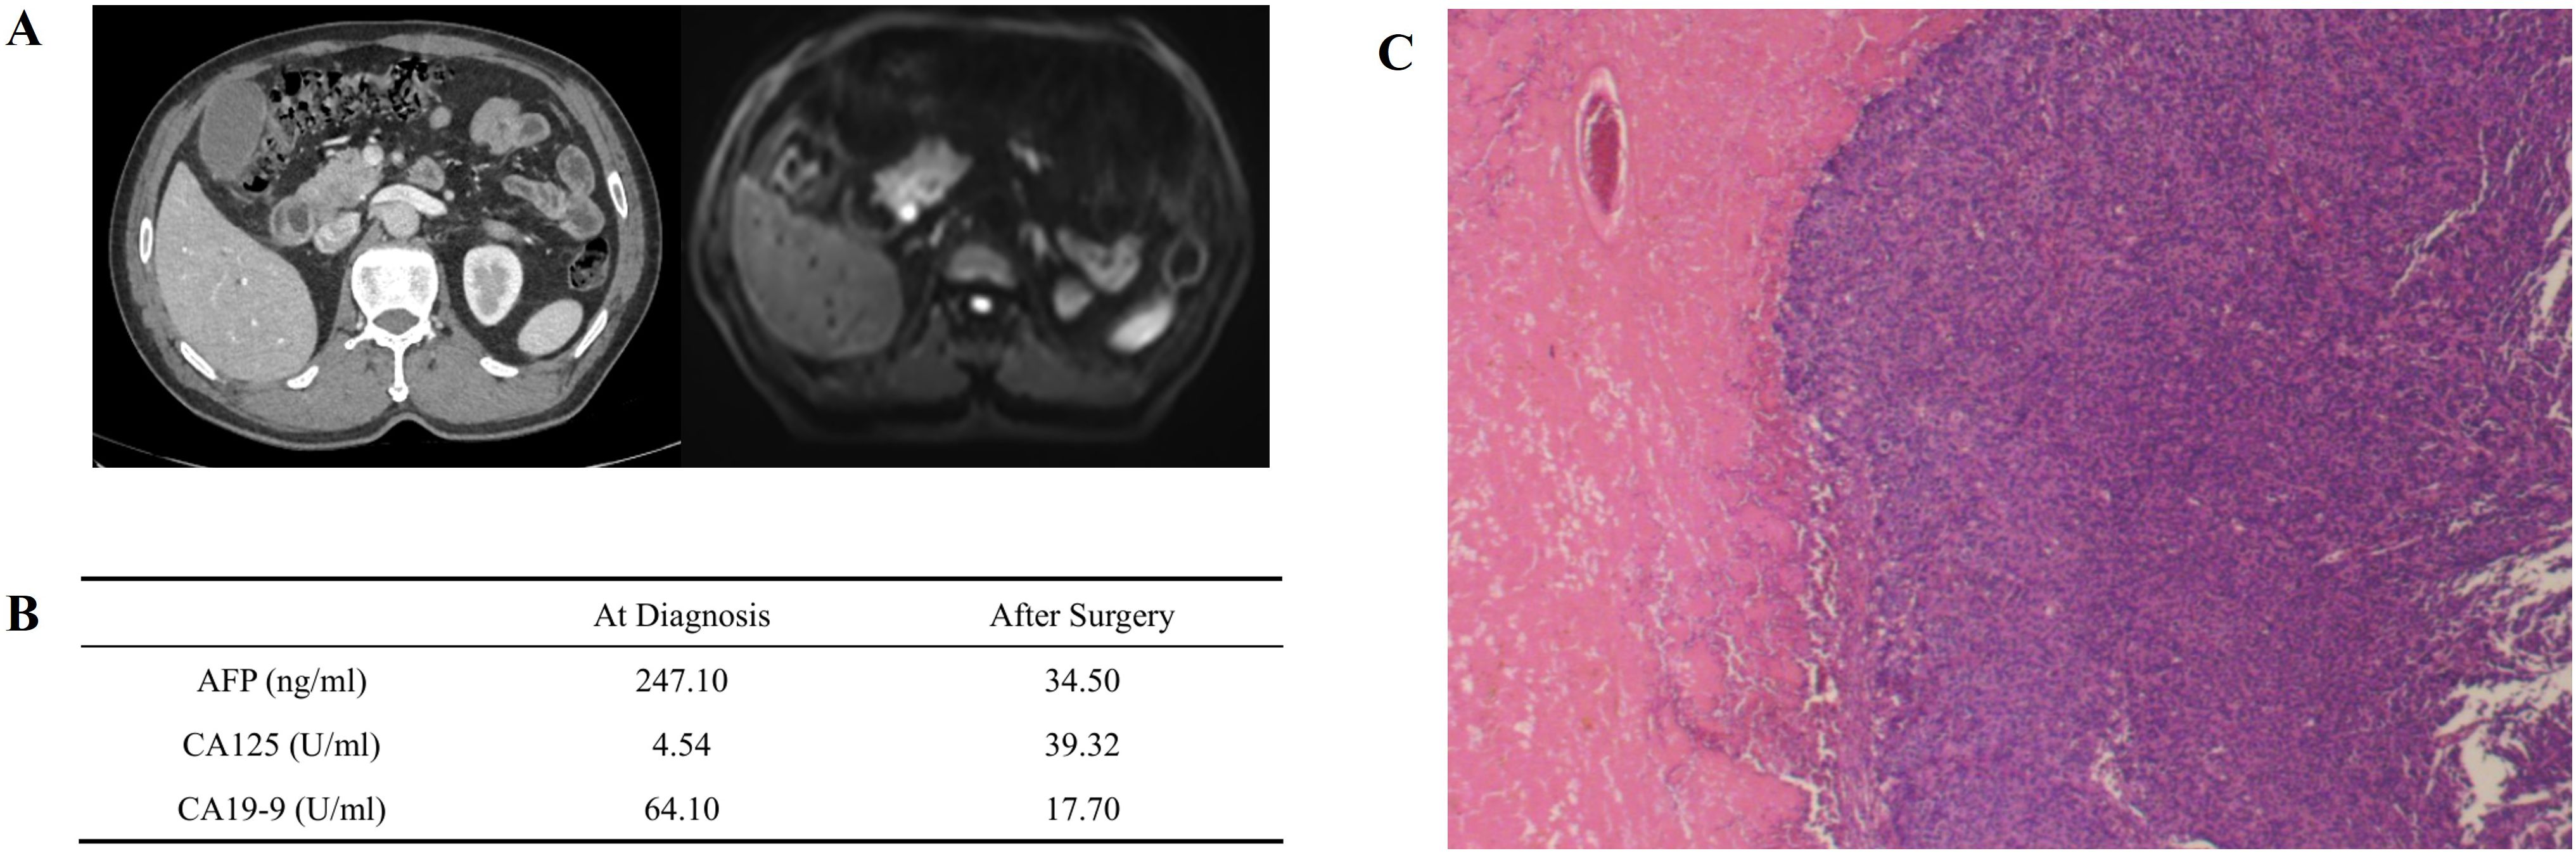

Pancreatic Acinar Cell Carcinoma (PACC) is a rare subtype of pancreatic cancer, and its systematic treatment protocol is still pending for further exploration. There have been a few reports that PACC patients benefited from immunotherapy-integrated treatment. Here, we present a metastatic PACC patient who had new hepatic lesions but lowered serum AFP and CA19-9 after 2 cycles of integrated treatment that included chemotherapy, PD-1 blockade and antiangiogenic therapy, which was later confirmed to be pseudoprogression (PsP) by pathological diagnosis. So far as we know, this is the first reported PsP case of PACC. This case highlighted the value of biopsy in distinguishing PsP from authentic tumor progression of PACC.